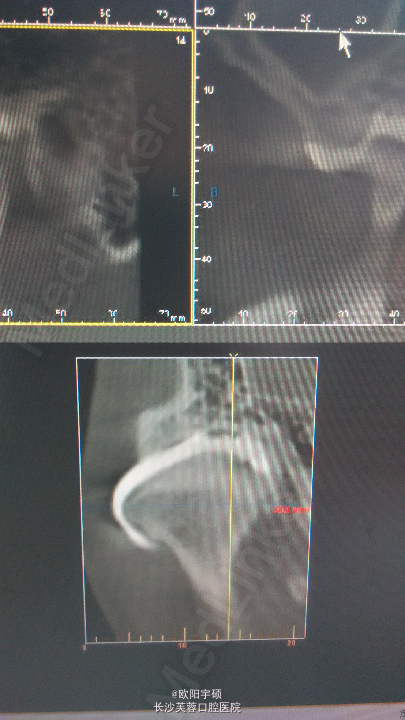

双侧关节区压痛,可闻及弹响,被动主动张口4.1cm,前牙开合,外院全景片显示双侧髁突短小,前斜面吸收明显,CT造影显示双侧关节盘穿孔可能性大

入院诊断左侧TMD,出院诊断双侧TMD,治疗为双侧双侧颞下颌关节盘穿孔修补术,关节盘松解复位术,髁突磨削术,关节成形术